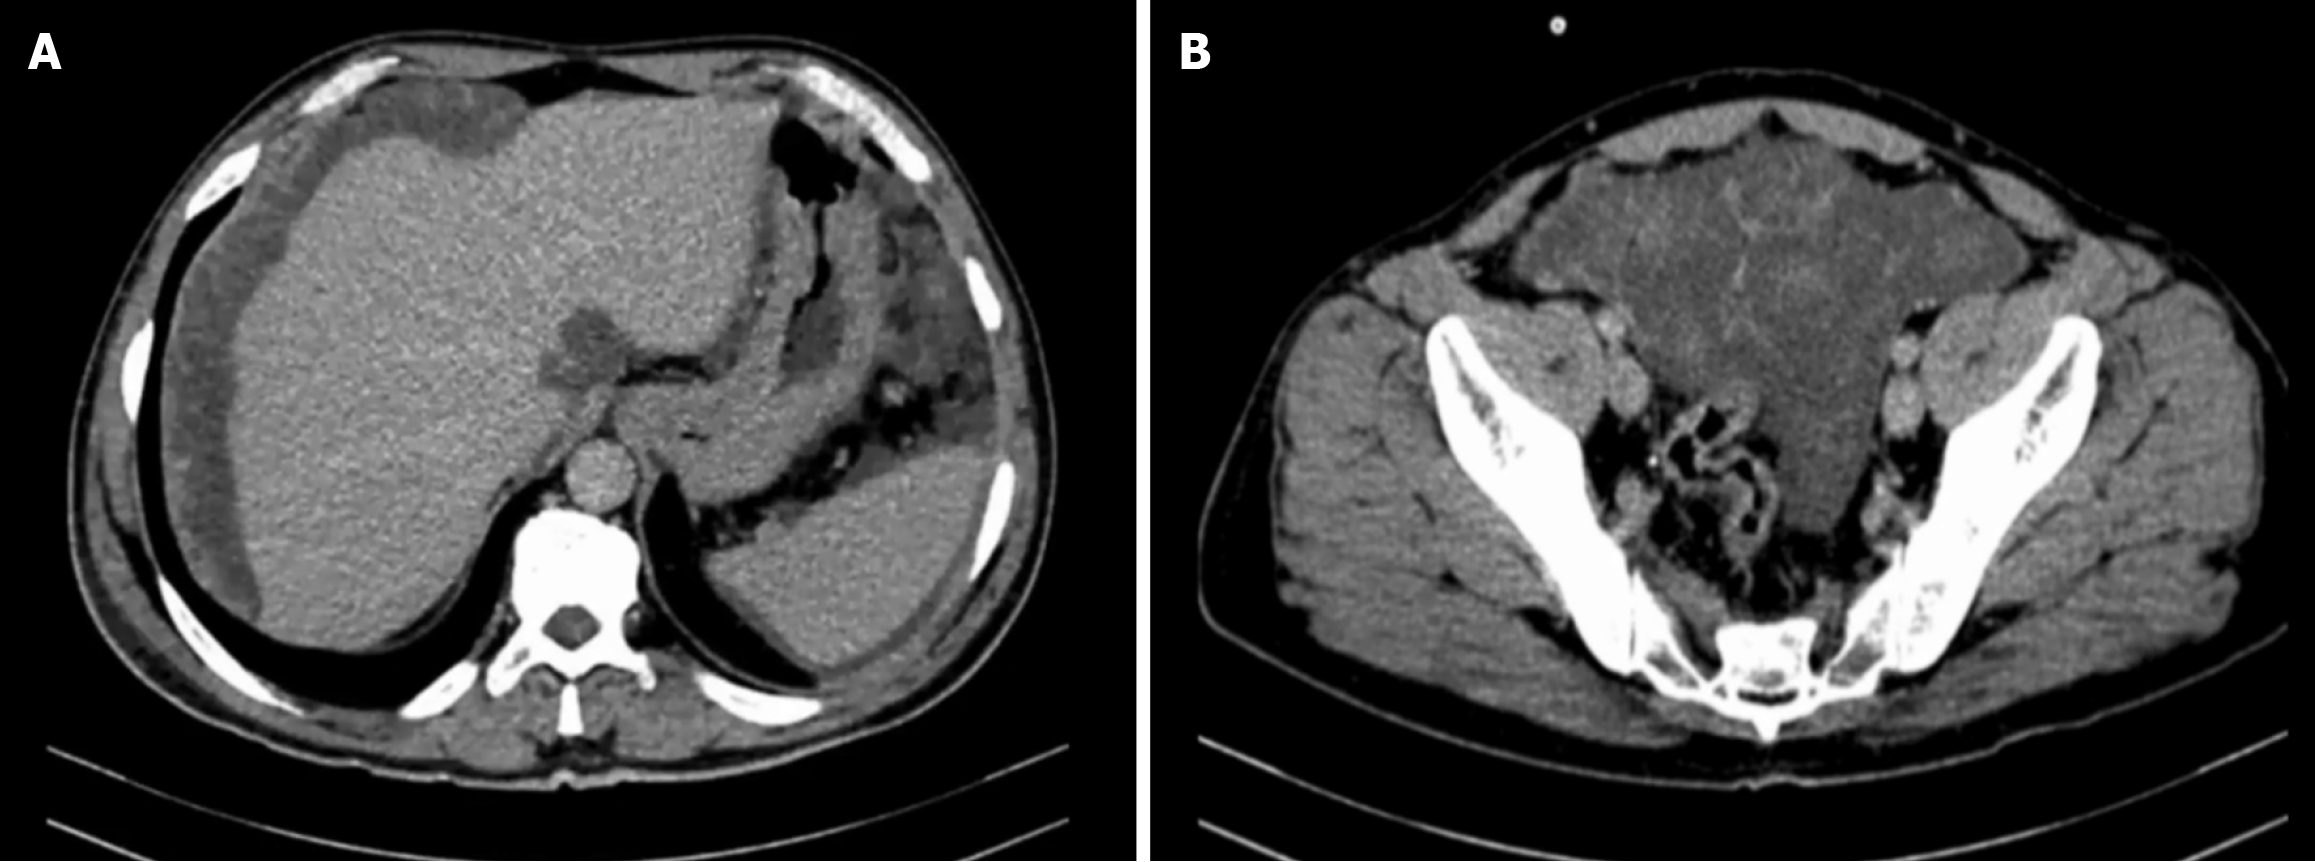

Figure 4 Enhanced computed tomography scan of the abdomen and pelvis.

A: Scalloping of the liver surface; B: Omental caking.